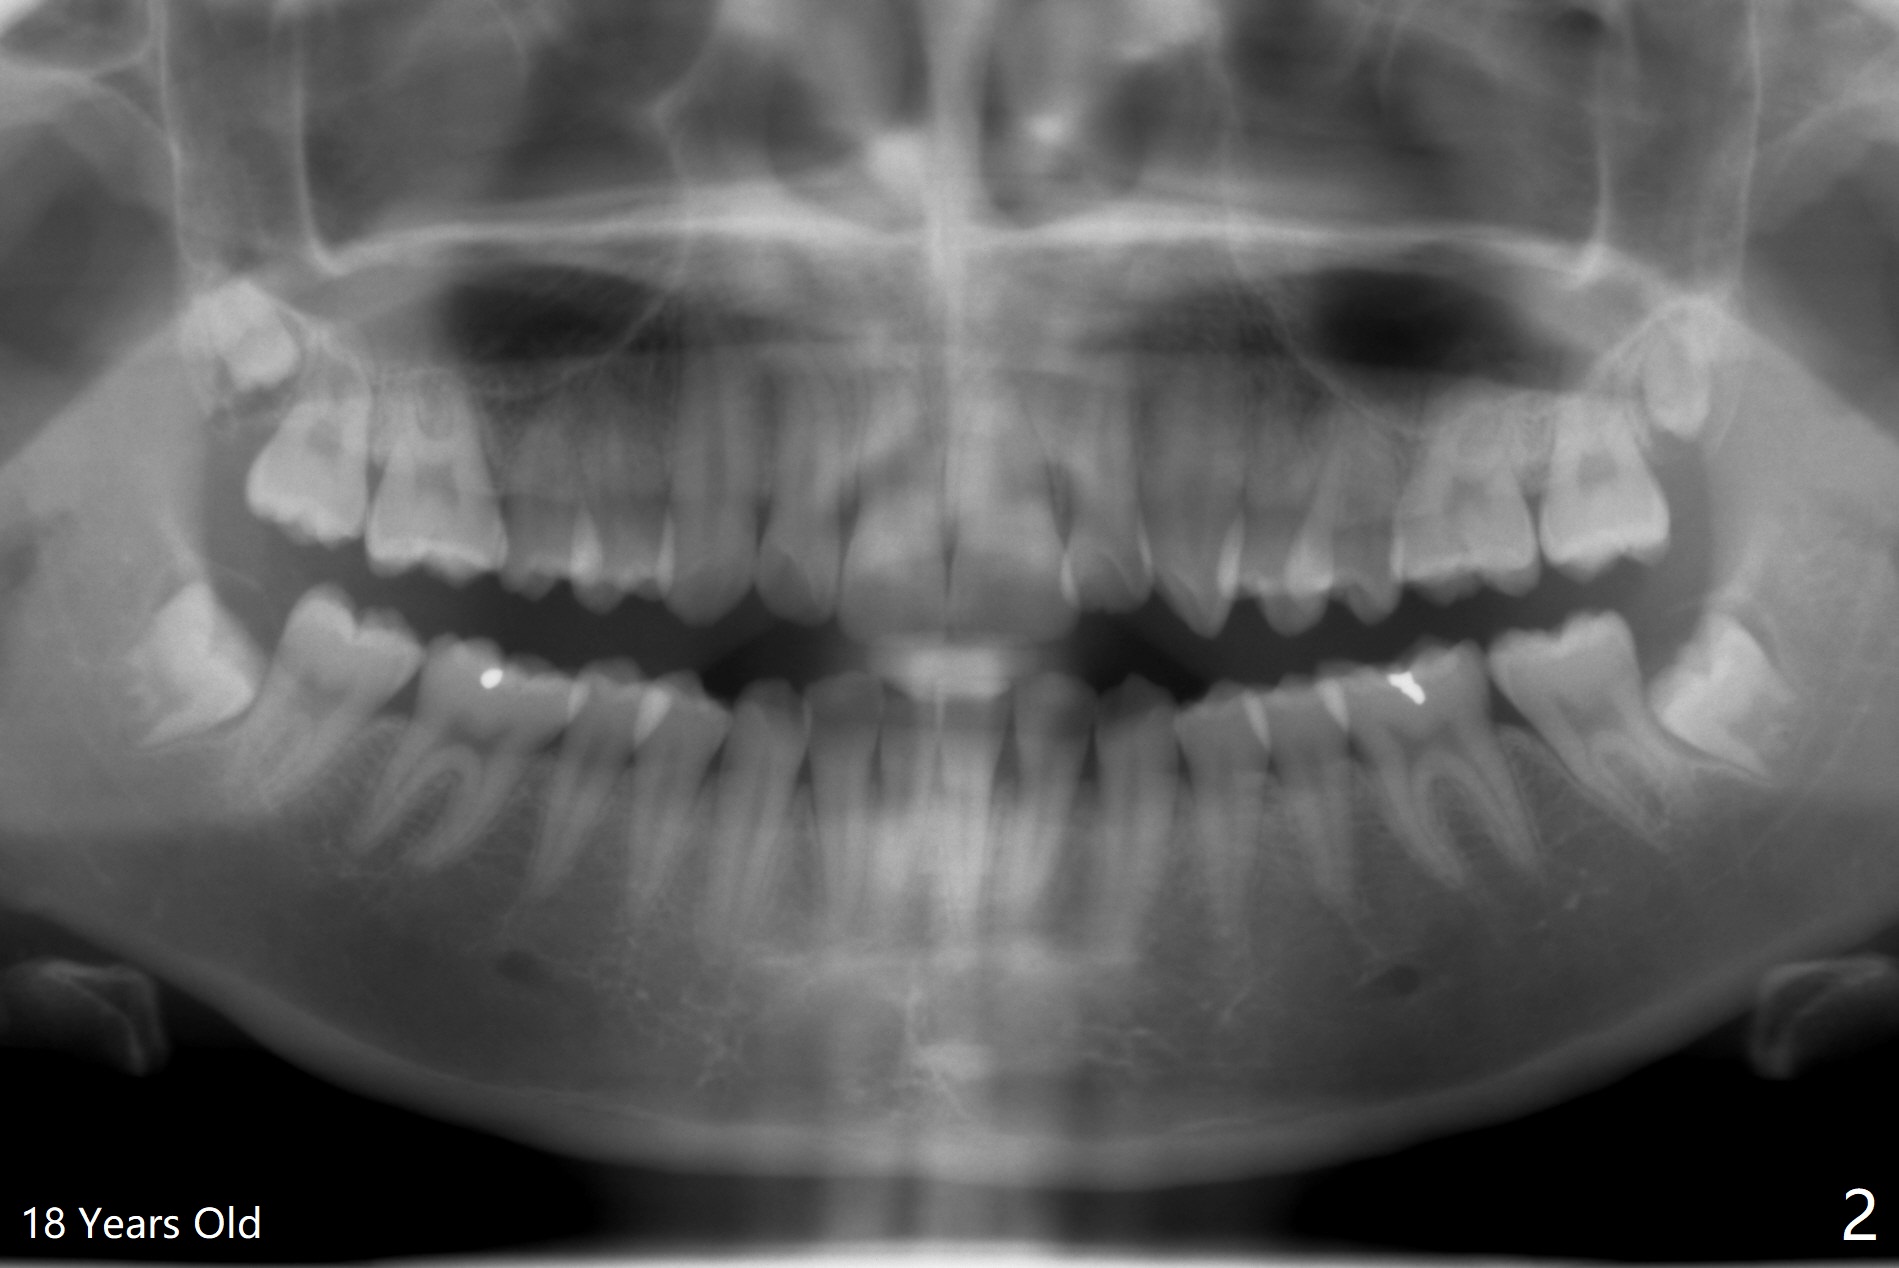

A 25-year-old woman, under our care for the last 11 years (Fig.1-6), returns for #1 and 32 extraction (1 year after #16 and 17 extraction (Osteogen plug)). Preop PA shows that a portion of the lower impacted tooth may be located buccal to the tooth #31 (Fig.4 black dashed line). An accessory incision is moved from distobuccal to midbuccal (Fig.7 arrowheads) to reduce postop loss of bone graft (Fig.8 B) from the incision. In fact the incision should be further moved to mesiobuccal (Fig.9 red line) if buccal impaction is suspected (curved black line). The buccal impaction of #32 of her father is more severe.